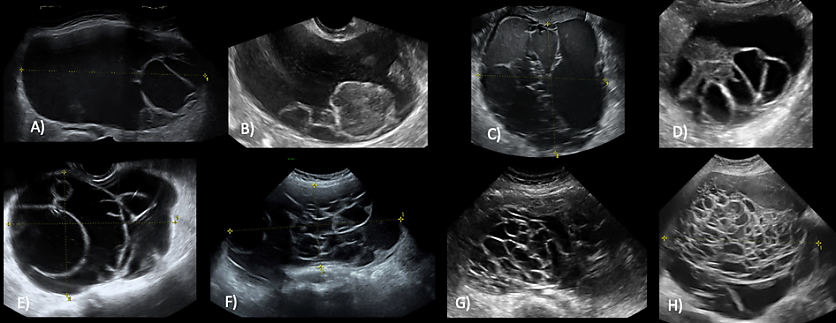

Mucinous BOTs (previously called intestinal type BOTs) are generally multilocular (80%) or unilocular (15%) and are typically large, with a median diameter of 195 mm. They feature multiple small loculi, often resembling a 'honeycomb appearance' and contain low-level cystic fluid without papillations (Figure 3).

3

Grayscale sonographic images of mucinous borderline ovarian tumors, appearing as multilocular cysts. From A) to H) there is an increase in the number of locules, varying from a cyst with <10 locules to a multilocular cyst with a marked honeycomb appearance.